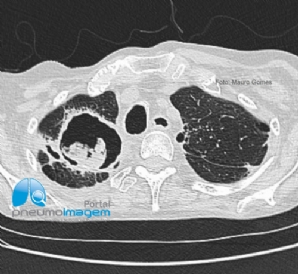

CASO CLÍNICO #57

Paciente masculino de 64 anos, tabagista com dispneia, tosse persistente e a seguinte imagem radiológica. Qual o nome desse sinal e o provável diagnóstico? Deixe seus comentários abaixo! *** A 64-year-old male smoker with dyspnea, persistent cough and the fo...